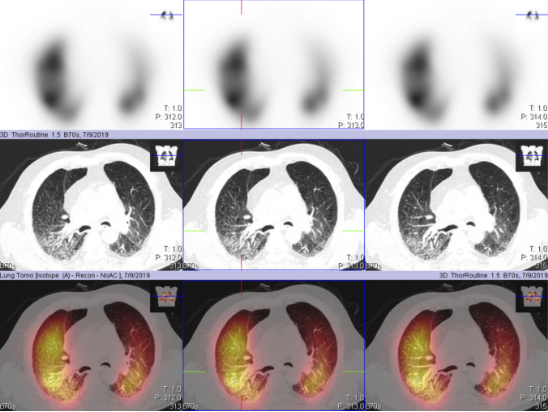

肺灌注SPECT-CT断层融合显像是同机进行肺灌注SPECT显像与诊断级肺CT显像,通过图像融合能够从不同的断面观察肺部血流灌注情况,诊断级CT图像还可以深入了解肺部组织结构情况,同机两种模式的图像融合做到了一站式服务,即方便了患者,又可为临床提供有效的诊断信息。

SPECT-CT断层图像融合显像